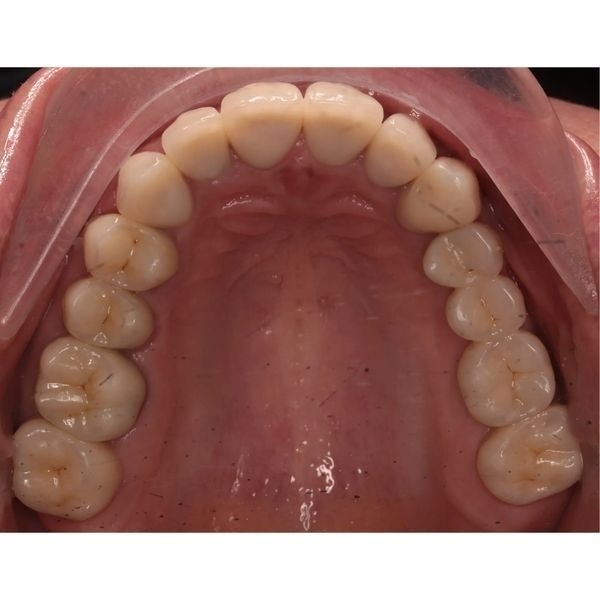

Когда суставные головки приняли нормальное положение, наступил этап изготовления постоянных конструкций. Из непротезированных зубов у пациентки остались только нижние 4 резца и 2 клыка.

Так как женщина хотела самые тонкие виниры с минимальной обработкой, ей установили ультраниры. Из-за поднятия прикуса и значительной стёртости зубов серьёзного препарирования не потребовалось, достаточно было под микроскопом сгладить острые грани и обозначить границы будущей конструкции для техника. Так удалось максимально сохранить твёрдые ткани зуба.

За весь период реабилитации пациентке:

- зафиксировали коронки и виниры на все зубы.